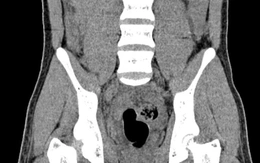

Đi viện muộn, cậu bé 14 tuổi mất tinh hoàn vì lỡ 'giờ vàng'

Xoắn tinh hoàn là cấp cứu tối khẩn, nhưng nhiều trẻ đến viện quá muộn. Trường hợp cậu bé 14 tuổi buộc cắt bỏ tinh hoàn là lời cảnh báo đau lòng.